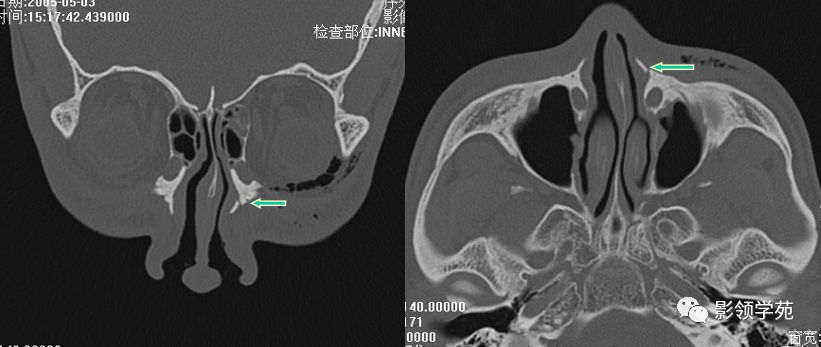

右侧鼻骨骨折

左上颌骨额突骨折

双侧鼻骨骨折

双侧上颌骨额突骨折